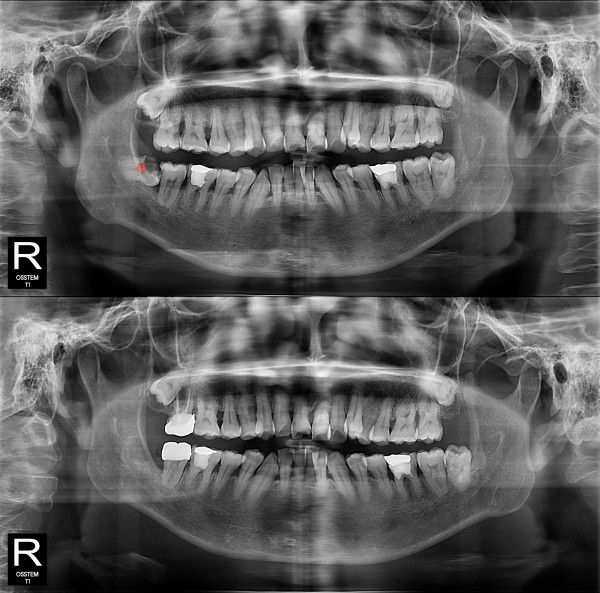

사랑니발치 충치가 심한 사랑니

826e40416d712e6cd444a78bde93df4b_1767857930_3003.jpg